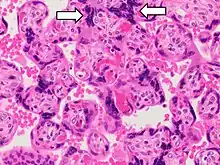

- Histopathology of placenta with increased syncytial knotting of chorionic villi, with two knots pointed out.